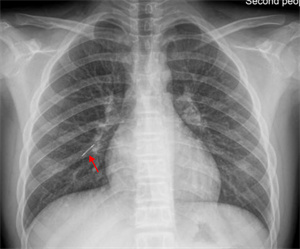

10月18日夜间急诊,来了一位14岁小患者,他在将手表零件放口中玩耍时,不慎吸入气管内。气管内异物是十分危急的,随时可能危及生命。小患者自觉胸闷不适,不时有咳嗽。急诊胸片和CT可以清晰地显示位于右中叶内侧段一长约2.3cm针形异物,两端较尖,急诊科医生程争启紧急联系呼吸与危重症医学科会诊,白克林主任考虑金属异物锐利可能损伤肺内血管造成大出血,准备急诊行内镜取异物。疼痛科、内镜室医务人员迅速反应,立即从家中赶往医院,争分夺秒做好各种术前准备工作。

鲜美的动物骨髓深受很多人喜爱。一位中年患者清晨急匆匆来到我院呼吸科住院部。主诉前一天晚餐吸食猪骨髓时,不慎将食物吸入气管,出现反复剧烈咳嗽,并有咯血。我院呼吸科医生在其急诊胸部CT中发现右中间段支气管有一 “刀片样异物” 横在管腔内。评估病情并做好预案后,医生顺利取出一锐利骨片异物,有效阻止了 “利器” 造成肺内出血恶果的发生。